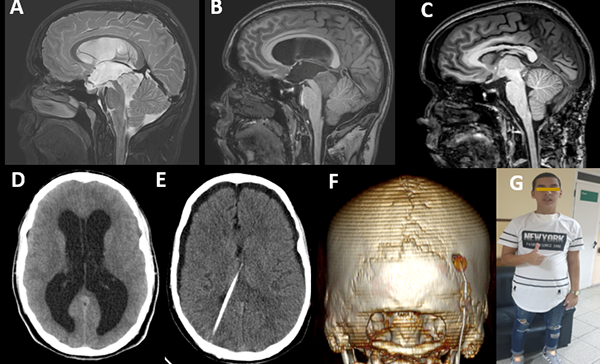

Se presenta un paciente masculino de 22 años de edad, de manualidad diestra y procedencia urbana, con antecedentes de cefalea holocraneal progresiva, nocturna y opresiva de 3 meses de evolución, asociada a vómitos ocasionales. Al examen físico se constató una puntuación según la Escala de Coma de Glasgow de 15 puntos y disartria como única manifestación positiva. La Tomografía Computarizada (TC), de urgencia, permitió observar dilatación de los ventrículos laterales y el tercer ventrículo, con edema periventricular y una lesión redondeada, isodensa y homogénea a nivel de la región pineal, correspondiente a una hidrocefalia obstructiva triventricular secundaria a un tumor en región pineal (figura 1 D). La RMI de cráneo de 3T evidenció además de la dilatación ventricular referida una lesión en región pineal hipointensa en la secuencia ponderada en T1 sin captación de contraste (figura 1 B) e hiperintensa en la secuencia ponderada en T2 (figura 1 A), de límites bien definidos con compresión y colapso del acueducto de Silvio, y efecto de masa sobre el vermis cerebeloso, que medía 26 mm x 27 mm x 23 mm en los diámetros anteroposterior, altura y transversal respectivamente. Se realizaron marcadores tumorales en suero y líquido cefalorraquídeo (LCR) los cuales resultaron negativos al igual que la citología del LCR.

Figura 1:

A) Corte sagital de RMI preoperatoria potenciada en T2. Se observa la lesión hiperintensa en región pineal. B) Corte sagital de RMI preoperatoria potenciada en t1 con Gadolinio. Obsérvese la ausencia de captación de contraste y la presencia de la vena de Galeno por encima de la lesión. C) Corte sagital de RMI enT1 postoperatoria donde se aprecia la resección total de la lesión. D) TC axial postoperatoria observándose la hidrocefalia obstructiva a pesar de la tercer ventriculostomía endoscópica. E) TC axial donde se observa la colocación del catéter ventricular y la resolución de la hidrocefalia. F) Reconstrucción tridimensional de la TC postoperatoria donde se observa el área de la craneotomía. G) Fotografía postoperatoria del paciente.

Se practicó en un primer tiempo quirúrgico tercerventriculostomía endoscópica y biopsia de la lesión de región pineal la cual no fue concluyente. Durante el postoperatorio inmediato presentó, nuevamente, síntomas de hipertensión endocraneana, por lo que se realizó derivación ventrículo peritoneal (válvula de media presión) sin otras complicaciones (figura 1, D y E). El paciente mejoró los síntomas de hipertensión endocraneana, y 7 días después se le realizó el proceder quirúrgico definitivo a la lesión.

Bajo anestesia general orotraqueal y cateterización venosa central, línea arterial y sonda vesical se colocó al paciente en posición de semisentado (figura 2 A) y se fijó el cráneo con soporte de Mayfield. Luego de la asepsia y antisepsia con iodopovidona se realizó una incisión en línea media suboccipital desde la protuberancia occipital externa hasta la apófisis espinosa de C4 (figura 2 B). Se realizó disección de las partes blandas con electrobisturí sobre la línea media (ligamento nucal), y se desinsertó la musculatura paravertebral esqueletizándose la escama del occipital desde el inion hasta el borde posterior del agujero Magno. Las partes blandas se mantuvieron retraídas mediante 2 separadores de Adson. Se procedió a la realización de 2 trépanos a 3 cm lateralmente e inferiormente del inion, y con la combinación de fresado con drill de alta velocidad y el empleo de osteótomos de Kerrison, se completó una craniectomía de fosa posterior con el límite superior exponiendo el borde inferior de la prensa de Herófilo (figura 2 F). Se realizó hemostasia con empleo de cera hemostática. Se practicó una durotomía arciforme con base hacia la prensa de Herófilo y se colocaron puntos de tracción dural (figura 2 C). A partir de este momento, se empleó la visualización completamente endoscópica, en la cual el primer ayudante sostuvo el endoscopio de forma bimanual, mientras el cirujano principal realizó la disección microquirúrgica bimanual. Se procedió a la identificación, cauterización y sección microquirúrgica de las venas puentes de línea media (figura 2 D). Al progresar la disección infratentorial supracerebelosa de las densas bandas aracnoideas, se identificó la vena precentral, la cual fue cauterizada y seccionada de forma alejada de su entrada a la gran vena de Galeno (figura 2 E). Se identificó el tumor de límites bien definidos, consistencia sólida y de aspecto blanco-grisáceo. Se cauterizó la superficie tumoral y se procedió al debulking intratumoral mediante el empleo de la aspiración, la pinza bipolar y ponches de biopsia (figura 2 F). Se practicó hemostasia rigurosa empleando electrocoagulación bipolar y lavado continuo con solución salina tibia durante este paso. Al completar el debulking, se procedió a la disección microquirúrgica del tumor de las estructuras neurovasculares adyacentes incluyendo la gran vena de Galeno, las venas cerebrales internas, la porción superior del vermis cerebeloso, y finalmente la lámina cuadrigémina y pared posterior del III ventrículo. Al completar la resección tumoral se verificó una hemostasia rigurosa, y luego de abundante lavado con solución salina isotónica se aplicó material hemostático (Equicel) (figura 2 G). Se practicó un cierre dural con poliéster 4.0 mediante puntos separados y se cubrió la duramadre con poliuretano. Se cerraron las partes blandas en múltiples planos con poliéster 1.0 y la piel se suturó mediante puntos de mayo empleando nylon 2.0. El tiempo quirúrgico fue de 8 horas y el sangrado transoperatorio de 300 ml. El paciente permaneció intubado durante 24 horas en la Unidad de Cuidados Intensivos. Posteriormente, permaneció en dicha sala durante 5 días hasta que fue trasladado a sala abierta de Neurocirugía. Clínicamente presentó un síndrome de Parinaud (parálisis de la mirada vertical). Los estudios postoperatorios mostraron la resección total de la lesión (figura 1 C). La estadía hospitalaria fue de 30 días. El informe anatomopatológico fue concluyente de tumor del parénquima pineal de diferenciación intermedia. Evolucionó satisfactoriamente (figura 1 G).